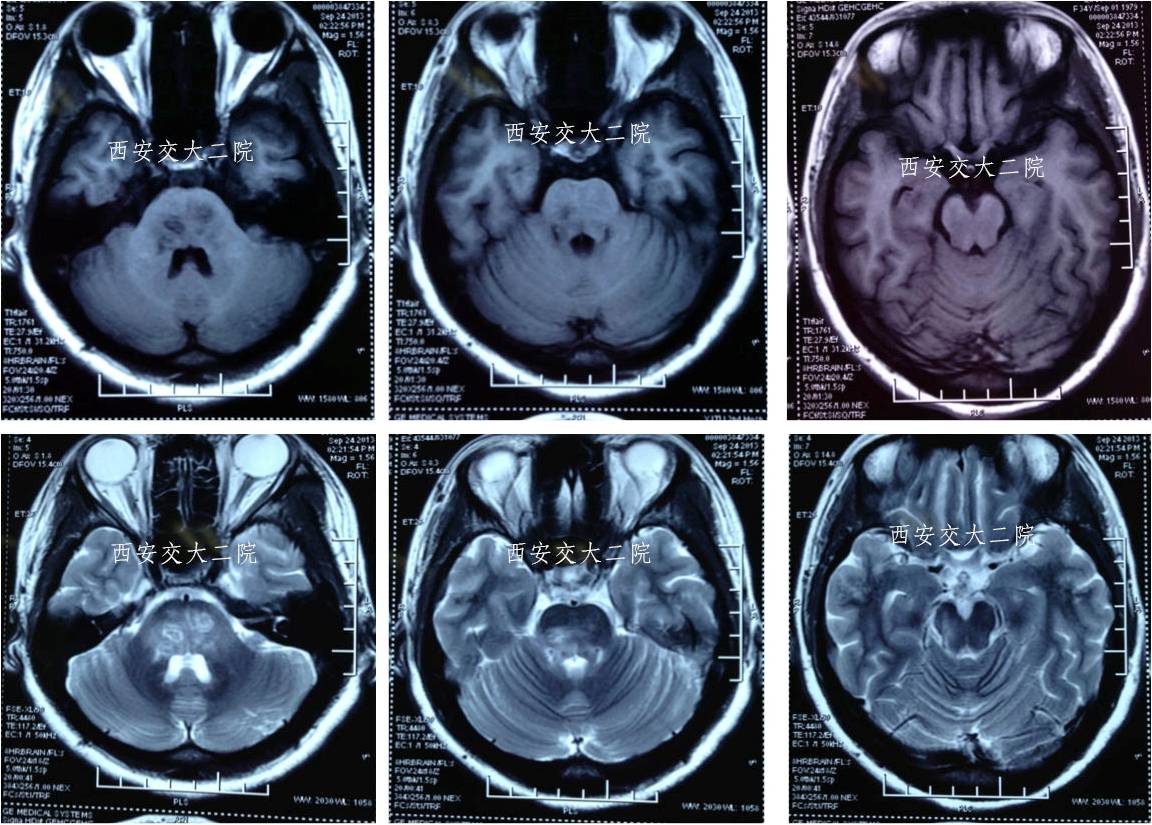

术前DWI

急诊脑CT